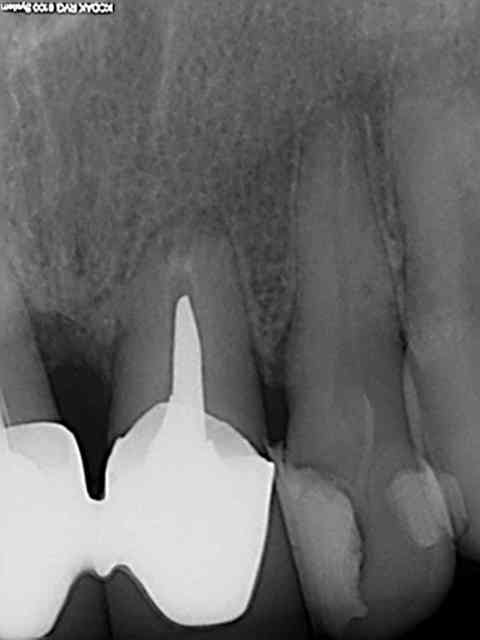

Que s'est-il passé sur l'endo 22 chicot, c'est mes yeux ou tu as bien dépassé ?

A priori oui, image bizarre en général ca fait un puff à l'apex.